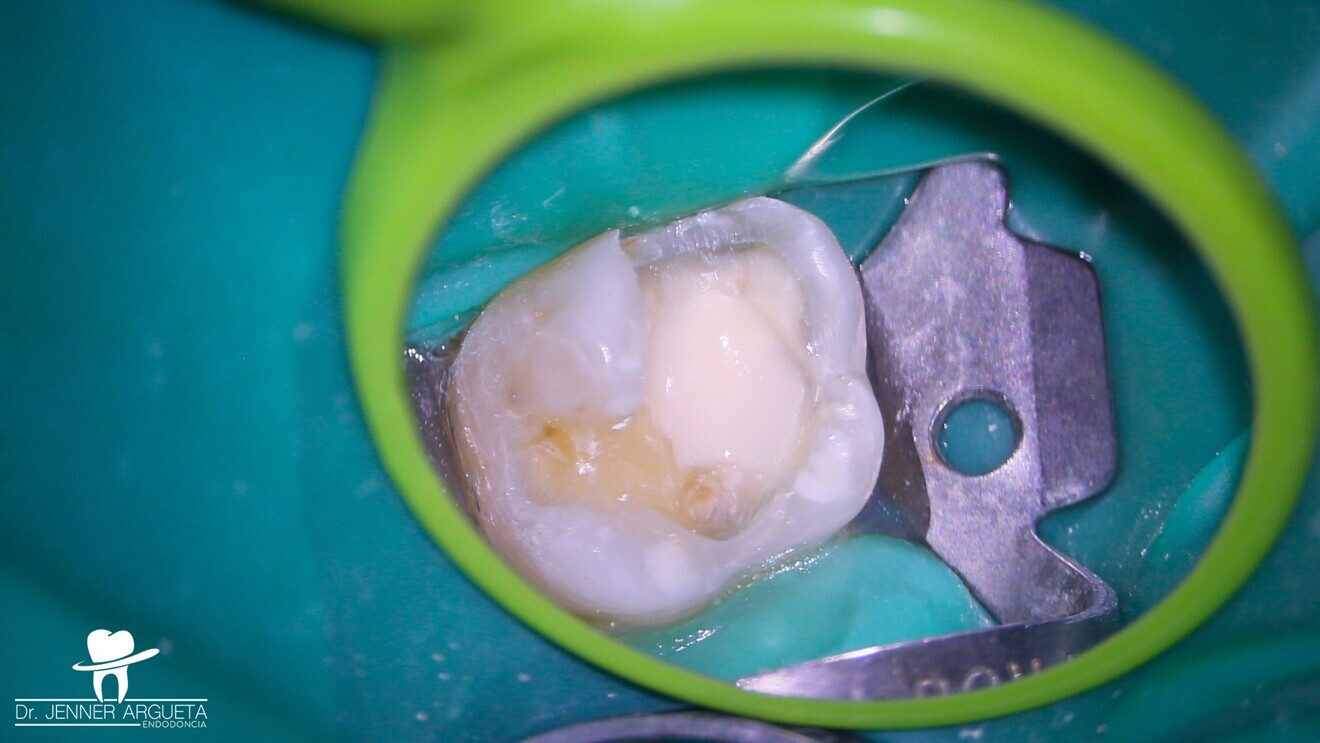

Fig. 3: Pulp exposure at the level of the cavity preparation floor with minimum haemorrhaging that was easy to stop.

Full isolation was achieved using a dental dam and a stainless-steel clamp, and flowable dam (NexTemp LC, Meta Biomed) was placed around the clamp to prevent bacterial contamination of the area to be treated. The temporary restoration material was removed circumferentially from the crown towards the cervical margin to limit the movement of bacteria to the pulp tissue space in case of pulp exposure.9 The mesiobuccal pulp horn was exposed while removing the caries (Fig. 3). It is always advisable to explore the cavity preparation floor with an endodontic explorer, because smaller caries-exposed pulps may be overlooked.